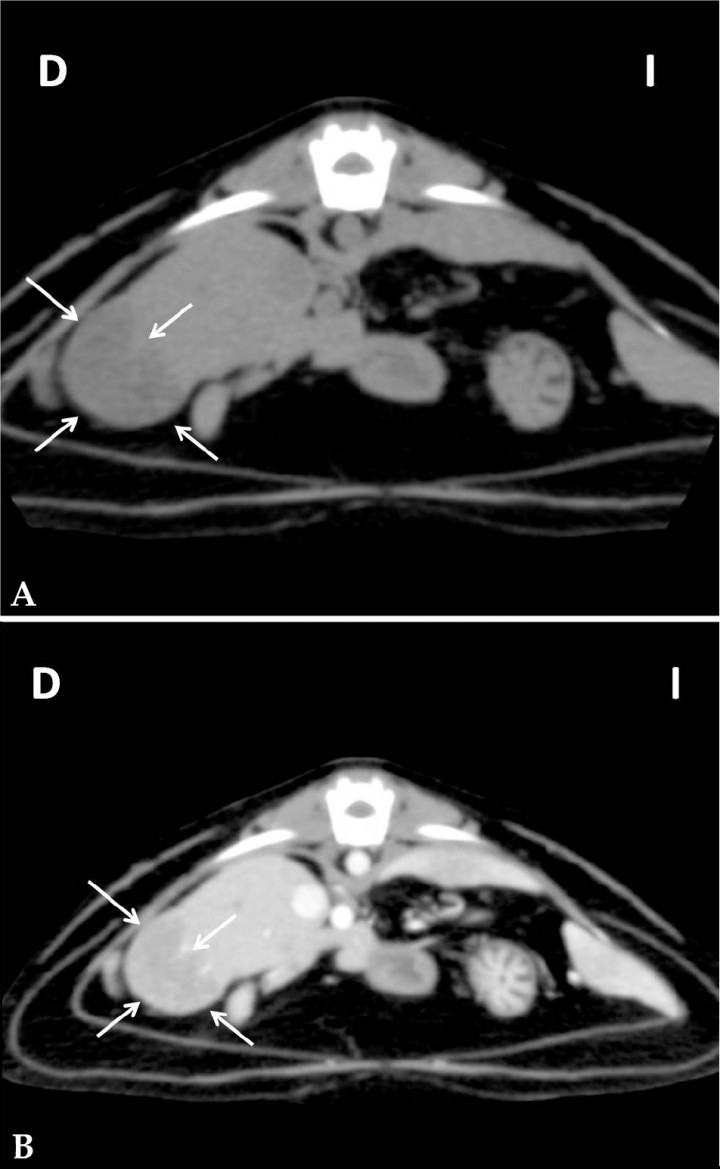

<p>Imagen tomográfica en corte transversal del abdomen en ventana tejido blando. (<strong>A</strong>) Secuencia precontraste. (<strong>B</strong>) Secuencia postcontraste intravenoso. Se observa una lesión hepática (flechas) de bordes irregulares e hipoatenuada que realza levemente tras la administración de contraste intravenoso. D: derecha, I: izquierda.</p>

Figura 4

Imagen tomográfica en corte transversal del abdomen en ventana tejido blando. (A) Secuencia precontraste. (B) Secuencia postcontraste intravenoso. Se observa una lesión hepática (flechas) de bordes irregulares e hipoatenuada que realza levemente tras la administración de contraste intravenoso. D: derecha, I: izquierda.

La TC confirmó la presencia de un vaso anómalo de gran calibre con origen en la vena esplénica que se dirigía caudalmente y que, tras un recorrido extremadamente tortuoso, se dividía, craneal a la vejiga de la orina, en tres vasos de menor calibre: dos se dirigían hacia caudal hasta insertarse en la vena ilíaca externa derecha y el tercero lo hacía en la vena ilíaca externa izquierda (Fig. 3). Estos hallazgos fueron consistentes con la presencia de una comunicación portosistémica extrahepática con origen en la vena esplénica e inserción múltiple en las venas ilíacas externas. También se visualizaron a nivel hepático varias lesiones de entre 2,5 y 4 cm aproximadamente, hipoatenuadas y de bordes irregulares. Tras la administración del contraste intravenoso se observó un realce leve y heterogéneo de las mismas y moderadamente inferior al del parénquima hepático (Fig. 4). Los diagnósticos diferenciales para estas lesiones fueron los mismos que los descritos previamente en los hallazgos ecográficos.